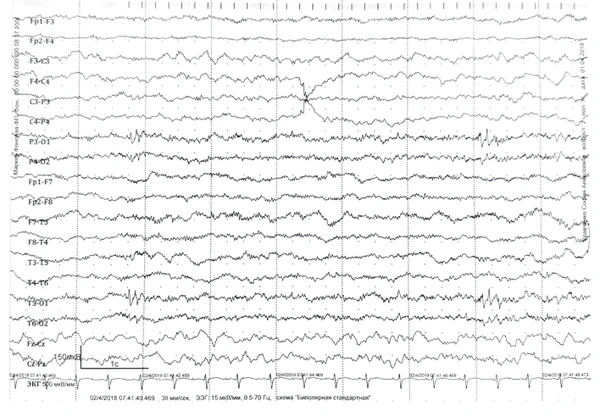

При проведении электроэнцефалографии (ЭЭГ) у пациентов с СД выявляется ряд характерных изменений: регистрируется замедление основной фоновой активности с доминированием тета-ритма частотой 4—5 Гц. В межприступном периоде у 70 % пациентов отмечается патологическая эпилептиформная активность, которая может носить как диффузный, так и региональный (фокальный) характер. Примерно у половины больных наблюдается фотосенситивность — способность световых стимулов провоцировать эпилептиформные разряды на ЭЭГ и иногда сами приступы, в редких случаях возможна аутоиндукция пароксизмов ярким светом. Провоцирующим фактором для эпилептиформной активности также может служить закрывание глаз. Характерной особенностью является усиление данной патологической активности во время сна[1].

- замедление основной фоновой активности на ЭЭГ, сочетание диффузной и региональной эпилептиформной активностей, ранние проявления фотосенситивности;